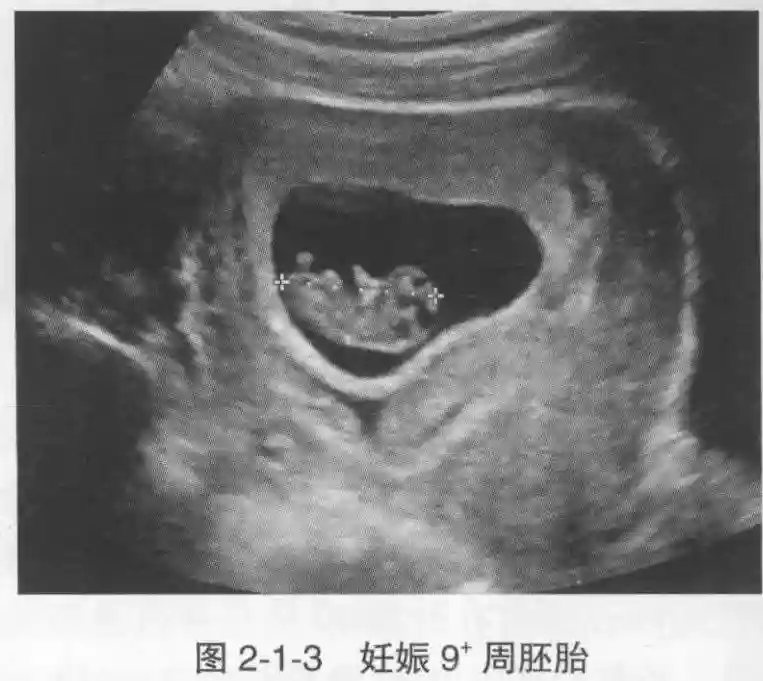

3??胚胎:胚胎通常在6-7周时可以为超声显示,起初为胎芽,表现为卵黄囊一侧局部组织增厚,达到1 -2 mm 时才有可能为超声测量出来。达4-5mm时可见胎心搏动,相应孕周为6-6.5周,妊娠囊大小为13-18mm。胚芽长度≥7㎜时仍未见心管搏动,提示胚胎停止发育。胚胎的出现和妊娠囊直径的关系:妊娠囊直径> 16 mm 时,经阴道超声应显示胚胎。妊娠囊直径> 25 mm 时,经腹超声均应显示胚胎。

4??胎心搏动:胎心搏动通常出现于6-6.5周,胚胎在4- 5mm就应该显示胎心搏动。